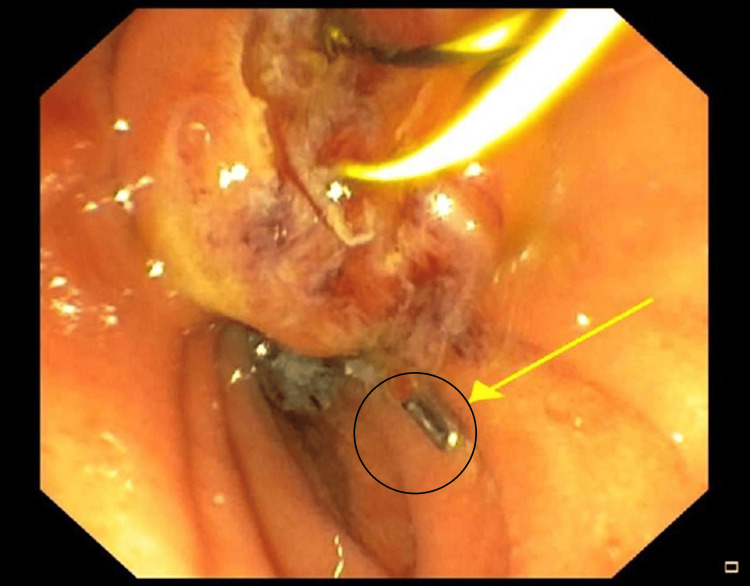

Given the finding of migrated clips causing biliary obstruction and cholangitis, broad-spectrum antibiotics were commenced and an endoscopic retrograde cholangiopancreatography (ERCP) was performed. Purulent bile, two stones, and three clips were found within the CBD (Figure 3). A sphincterotomy was performed, and with balloon extraction, all the stones and surgical clips were trawled out. The patient had an unremarkable recovery and was discharged three days post-ERCP with full resolution of symptoms.